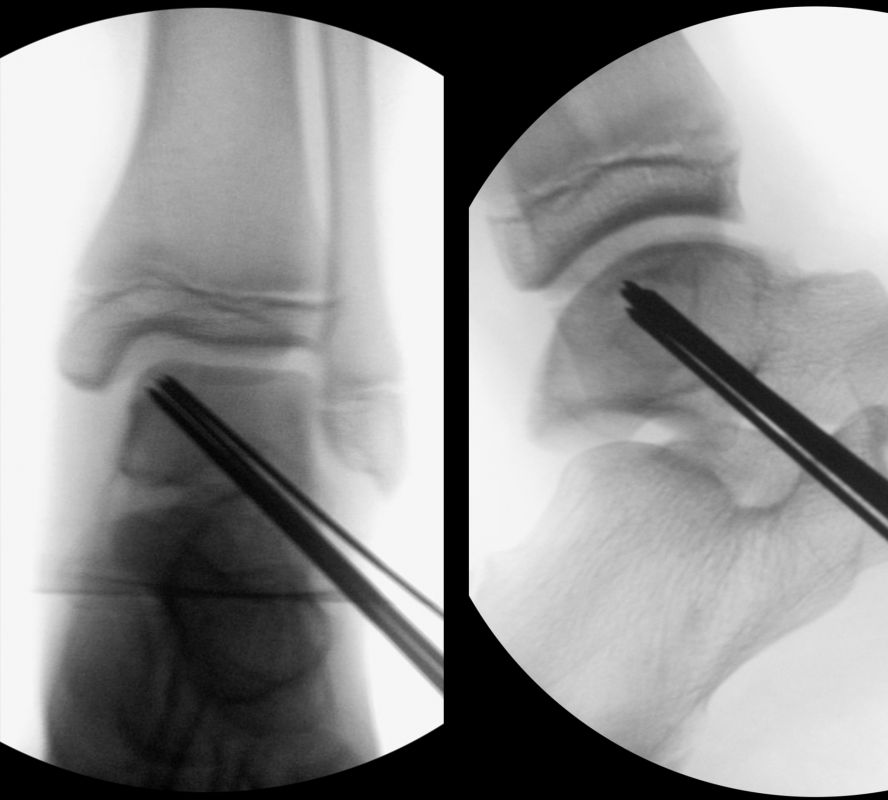

Dislozierte Frakturen (Frakturspalt > 2 mm) werden grundsätzlich operativ behandelt. Die Reposition kann arthroskopisch unterstützt erfolgen. Die Schraubenosteosynthese erfolgt entsprechend dem Frakturverlauf. Bei Twoplain Frakturen ist meist eine epiphysäre Schraube ausreichend die von lateral kommend das Fragment nach medial-proximal fixiert. Der Schraubenverlauf ist üblicherweise von lateral ventral nach proximal dorsal medial (Abb. 24). Nach Reposition darf in der seitlichen Aufnahme des Sprunggelenks, als auch in der 45° Außenrotationsaufnahme keine Stufe in Höhe der Wachstumsfuge erkennbar sein. Eine sichtbare Stufe ist Indikator für eine unzureichende Reposition.

Bei Triplane-Frakturen fasst die metaphysäre Schraube das metaphysäre Fragment einschließlich eines hinteren Volkmann Dreiecks, die epiphysäre Schraube fasst das epiphysäre Fragment. Da der Fugenschluss noch nicht abgeschlossen ist, sollten die Schrauben die Wachstumsfuge nicht kreuzen, obwohl eine Wachstumsstörung unwahrscheinlich ist (v. Laer 2013).